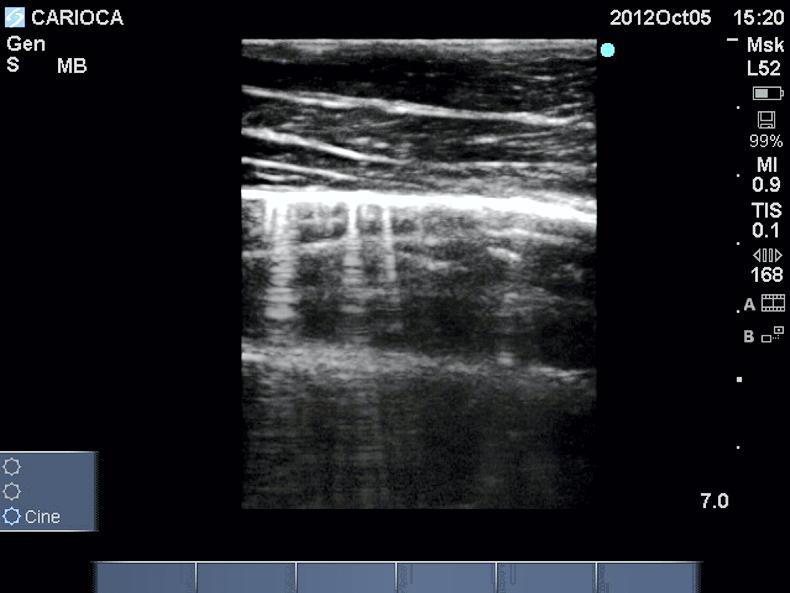

The diagnosis of larval cyathostomiasis is difficult as since it is caused by larval stages, these cannot be detected with a faecal egg count (FEC). An experienced clinician can use a combination of relevant case history, clinical signs and laboratory findings to come to a presumptive diagnosis and response to therapy is definitive in most cases. Ultrasonography can be used to detect thickening and oedema of the colon wall and this can then be used to monitor response to therapy.